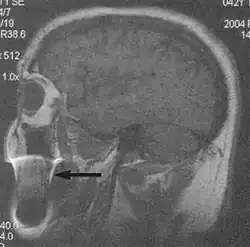

Flow can manifest as either an altered intravascular signal (flow enhancement or flow-related signal loss), or as flow-related artifacts (ghost images or spatial misregistration). Flow enhancement, also known as inflow effect, is caused by fully magnetised protons entering the imaged slice while the stationary protons have not fully regained their magnetization.[1] The fully magnetized protons yield a high signal in comparison with the rest of the surroundings. High velocity flow causes the protons entering the image to be removed from it by the time the 180-degree pulse is administered. The effect is that these protons do not contribute to the echo and are registered as a signal void or flow-related signal loss (Fig. 2).[1] Spatial misregistration manifests as displacement of an intravascular signal owing to position encoding of a voxel in the phase direction preceding frequency encoding by time TE/2.The intensity of the artifact is dependent on the signal intensity from the vessel, and is less apparent with increased TE.[1]